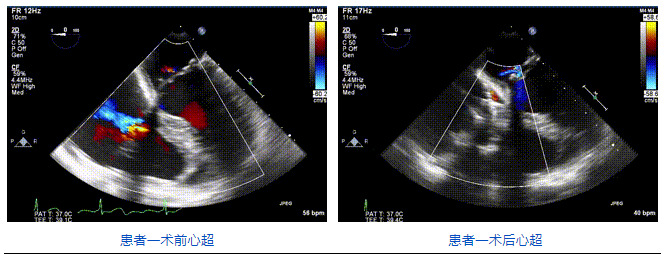

2021年12月24日,復旦大學附屬中山醫院葛均波院士團隊成功應用LuX-Valve Plus為一例極重度三尖瓣反流(TR)合并房顫、房缺的患者完成了經血管三尖瓣置換術,這是在前基礎上,本周完成的第三例經血管三尖瓣置換手術,葛均波院士、周達新教授等與心外科魏來教授、賴顥教授,心超室的潘翠珍教授、李偉教授及麻醉科的郭克芳教授共同完成了本周手術,均獲得圓滿成功!患者術后超聲顯示無TR,臨床癥狀明顯改善。本周手術的成功也為LuX-Valve Plus救治性臨床研究添上了濃墨重彩的一筆。

三例患者入院后,葛均波院士團隊周達新教授、潘文志教授、張源博士、陳莎莎博士及心超室的潘翠珍教授、李偉教授對患者的情況進行詳細評估和討論,最終決定為三例患者選擇LuX-Valve Plus40mm、50mm和50mm型號的瓣膜進行手術治療。手術后即刻拔除氣管插管,術后患者三尖瓣反流癥狀得到顯著改善,復查心超結果顯示人工三尖瓣瓣膜支架固定穩定,瓣葉關閉形態未見異常,未見明顯反流。